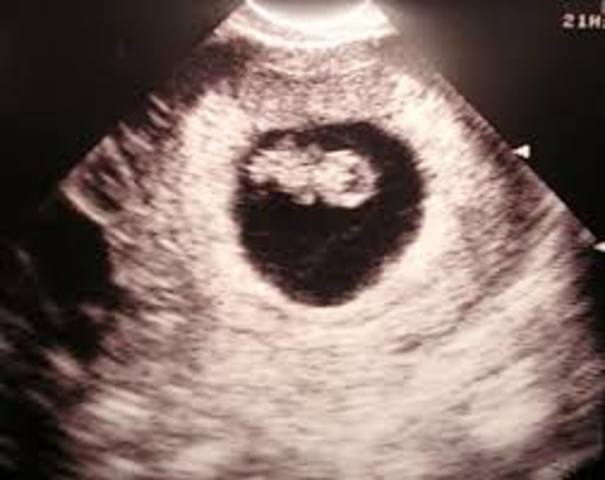

Esta formado por dos esferas huecas una interiior de la otra la extrea se llama saco corionico y la interna disco embrionario. La susutancias nutritivas "difusion". Circulación primitiva entre el embrion y la madre, entonces la sangre de estas le provee los elementos para la nutrició.

El embrion mide 2mm, siendo un disco valado posee 3 hojas de tejido (disco embrionario trilaminar).